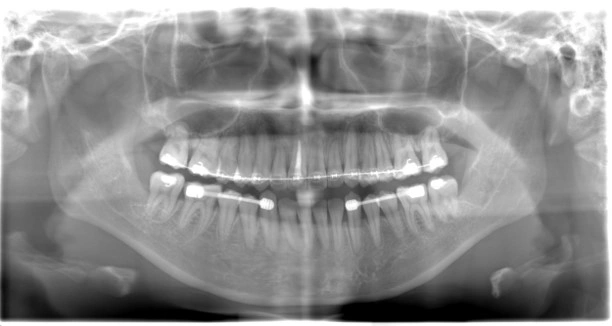

オールオン4 症例①

オールオン4 症例

治療例

オールオン4 症例②

オールオン4 症例③

費用例

総額 4,884,000円(税込)

年齢

60代女性

主訴

噛めない

治療期間

1年

施術(治療)内容

オールオン4と前歯2本のセラミック治療

リスク・副作用

外科的侵襲がある、費用が高い

麻酔費用

33,000円×3回=99,000円

治療費用

4,884,000円(税込)

4,785,000円(税込)